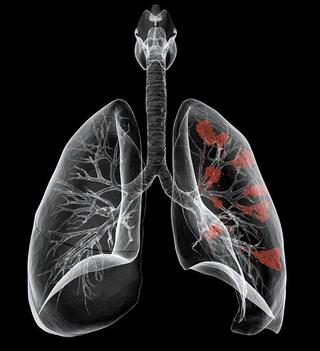

폐암은 전이가 쉬운 암으로 말기증상으로 뇌, 뼈, 간 등에 전이 되면 다양한 증상이 나타나게 돼요. 뼈에 전이 되면 어깨와 허리통증이 뇌에 전이 되면 뇌 기능 이상으로 인해 두통, 구토, 마비, 경련이 간으로 전이 되면 복부에 덩어리가 느껴지고, 황달, 전신 권태감 등이 발생합니다.

말기증상으로 어깨와 등, 허리에서도 통증이 나타날 수 있어요. 몸에 암이 전이 되었기 때문으로 뼈에 전이를 일으킬 경우 통증이 발생합니다. 주로 어깨와 허리에 통증이 있으며 숨을 마실 때 기침을 하거나 음식을 삼킬 때도 심한 통증이 동반됩니다.

폐암이 진행되어 말기가 될 수록 기침과 호흡곤란이 심해지게 되는데요. 암으로 인해 공기 통로가 압박되고 폐와 그 주위에 물이 쌓이는 폐부종이 되면 점점 기침이 심해지게 됩니다. 마치 폐가 물에 잠긴 상태로 매우 괴롭습니다.